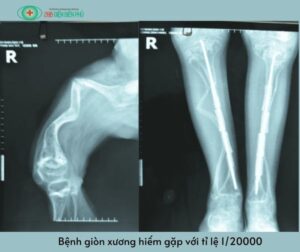

Bệnh tạo xương bất toàn là gì??

Xem nhanh nội dung Bệnh tạo xương bất toàn hay bệnh giòn xương ở trẻ là một bệnh lý hiếm gặp trên lâm sàng nhưng gây nhiều phiền toái. Bệnh đặc trưng với sự suy giảm chất lượng xương do thiếu hụt collagen trong cơ thể vì thế những đứa trẻ mắc bệnh thường xuyên bị